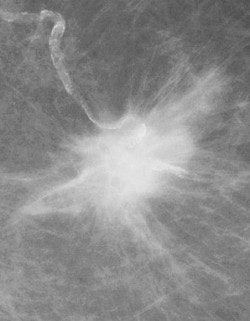

![]() ![]() |

FFDM images acquired on the Senographe 2000D, including zoom (middle) and magnification (below). Images courtesy of Dr. Wolfgang Matzek.